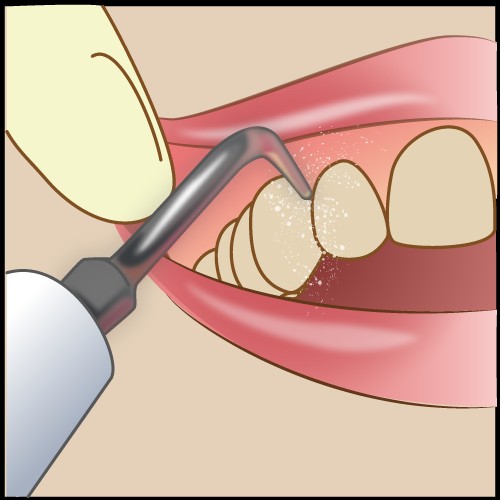

プロフェッショナルコントロール

これが定期的にきてもらってしていくケアーになります!

いわゆる歯石取りです!!

歯石取りは立派な治療行為なんですね!

歯石は細菌の住みかになるので除去すると細菌数が減ります!!

ぜひ、歯医者さんでとってもらってください!!